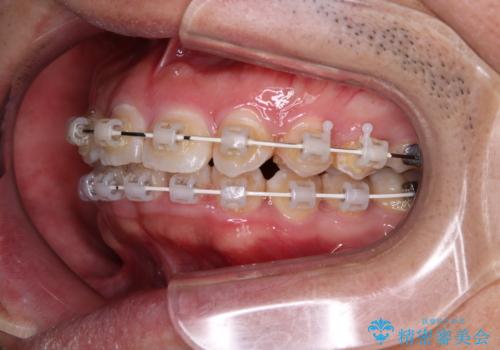

- 矯正装置

- 審美装置

- デコボコと奥歯の咬み合わせのズレを気にして来院された患者様です。

骨格的に、下顎が右側にずれており、左側の咬み合わせに鋏状咬合などのアンバランスが生じている状態でした。

また、上顎前歯に欠損が1本あり、上下ともに前歯部に叢生が認められ、下顎前歯の大半が隠れてしまうほどの過蓋咬合も認められました。

咬合平面を平坦にしながら前歯の咬み合わせを挙上し、デコボコと鋏状咬合も改善していくこととしました。